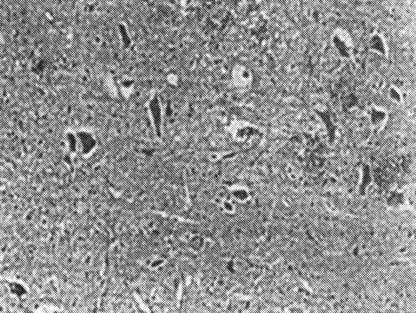

图19-3 光学显微镜下见神经纤维轴索肿胀,小灶出血及液化性坏死,灰质血管扩张出血,神经细胞变性(HE×200)

(2)不完全性脊髓损伤:脊髓不完全损伤后表现为灰质出血、水肿可波及白质,但程度较完全损伤为轻。白质中出血较少,神经纤维完整,神经细胞不完全退变。特点:①由于损伤程度不同,病理改变差异较大,轻者仅有部分灰质坏死,大部分白质保存良好,动物的脊髓功能可以大部分恢复;重者除灰质坏死外,白质中可以有囊腔、软化灶或胶质灶,但仍有部分白质保存良好,动物的脊髓功能仅部分恢复。②不完全性脊髓损伤,病变呈非进行性发展。伤后1~3h,中央管内渗出及出血,灰质中有数处点状或灶性出血,神经细胞及白质无何改变;6~12h灰质中仍呈点状或灶性出血,出血区部分神经级胞开始退变。白质轴突无改变或髓鞘水肿;24h少数白质轴突发生退变,灰白质形态清楚,无改变(图19-2、图19-3);4~8周,脊髓中已不见出血,神经细胞存在,少数仍呈退变,白质中有众多正常轴突,一部分轴突退变浊肿,少数空泡。较重的损伤,则有坏死囊腔。此后,病变无进行性发展,而是出血吸收,逐渐恢复脊髓功能。